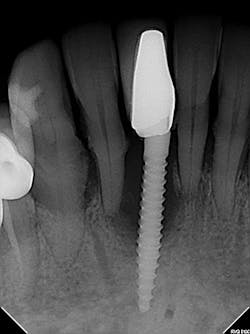

The most critical aspect of any implant system is the interface between the implant fixture and its surrounding bone (figures 1-5). Integration between the fixture and its surrounding bone is the foundation of modern implant dentistry. There is little we can do to modulate bone healing, but we can modify the implant fixture itself.

Figures 1-5: Figures 1 through 4 illustrate, respectively, a seven-year follow-up visit and a three-year follow-up visit of two different implant systems. Implant No. 22 (figure 5) shows peri-implant radiolucency following functional loading, indicating fibroencapsulation and loss of integration into bone, necessitating removal.